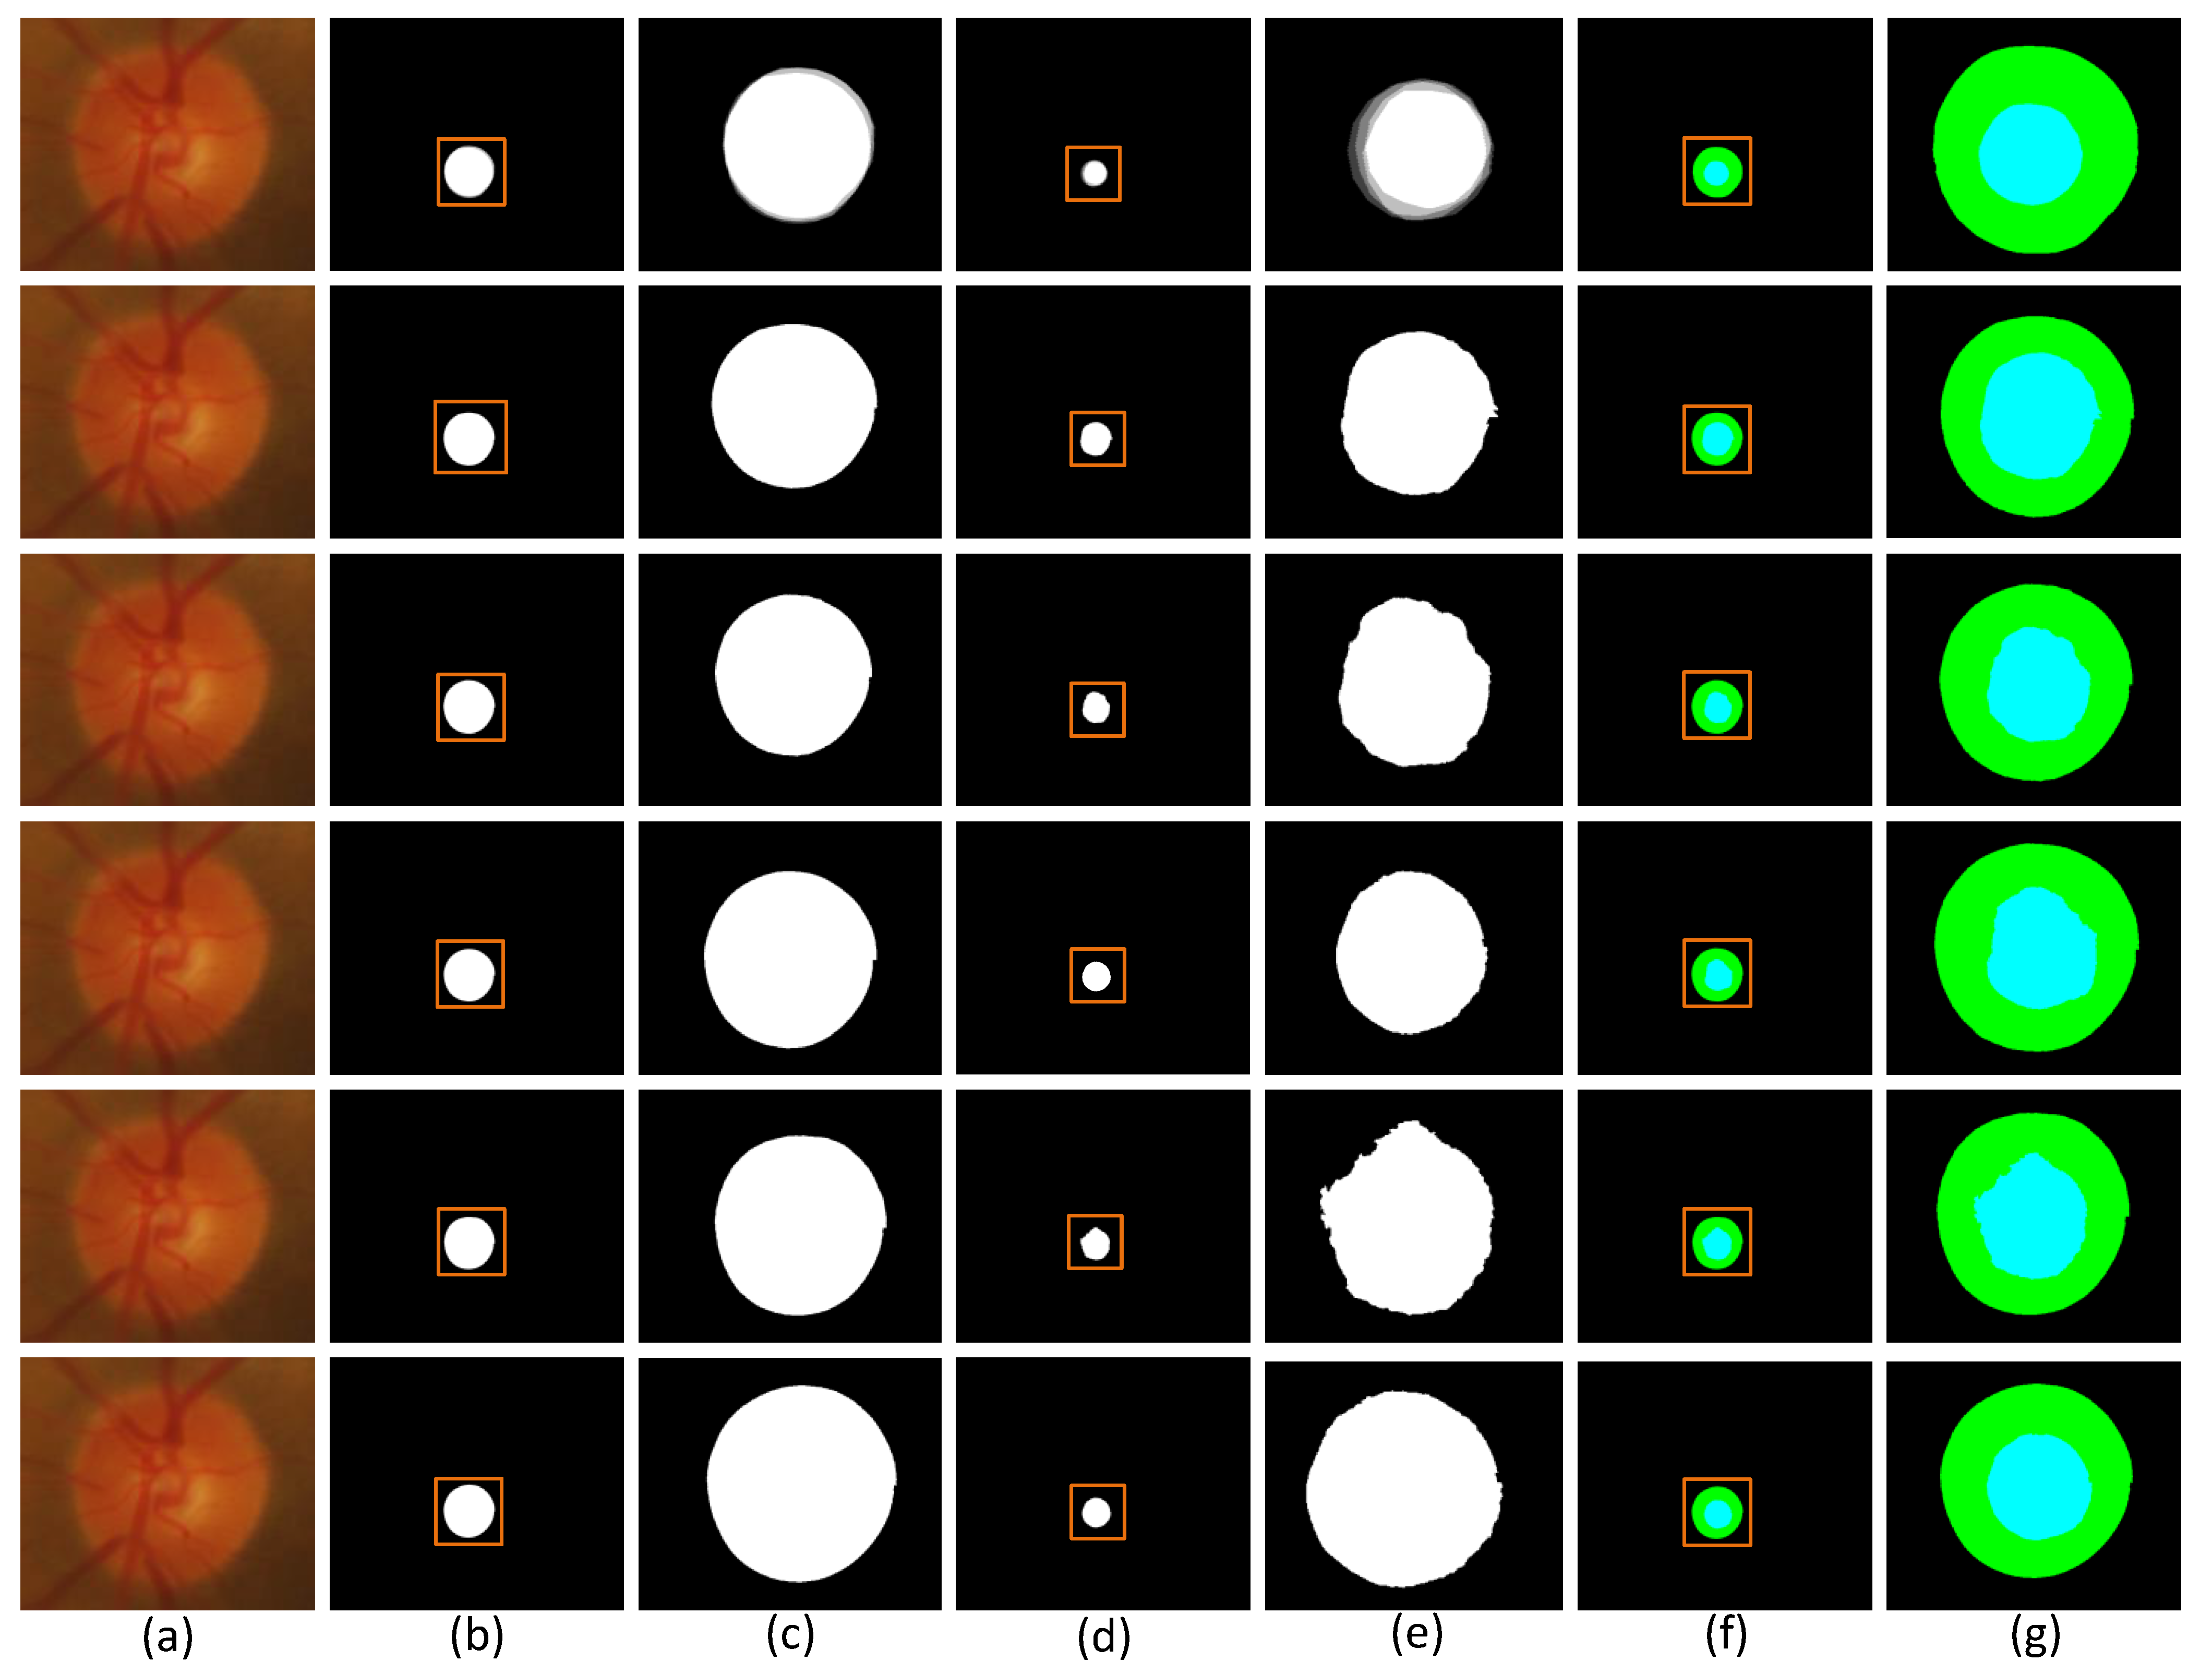

In order to observe the difference of segmentation results more visually, we compare the segmentation visualization images of each model in the ablation experiment. The advantages of MSMB-Net can be seen from the visualized images. Figure 7 and Figure 8 show the visualization results of each model for DRIVE, STARE, CHASE and Drishti-GS1 datasets, respectively.

Figure 7.

Different models at different segmentation results of visualization of the dataset: (a) column is Basic, (b) column is SMCF, (c) column is SMCF + SRL, (d) column is SMCF + MBCM + SRL, (e) column is MSMB-Net.

Figure 7 shows the comparison of the segmentation result images of each model on the DRIVE, STARE and CHASE datasets. In the figures, (1) shows the visualization results of random samples from the DRIVE test dataset, (2) shows the visualization results of random samples from STARE test dataset, and (3) shows the visualization results of random samples from the CHASE test dataset. The yellow boxes in the figure indicate that different network models have different effects on the local segmentation regions of the blood vessels. We can find some broken and mis-segmented vessel segments by zooming in on the yellow box. At the same time, it is observed that the combination of SMCF modules has a certain repair effect on the break of small blood vessels than the combination without these modules. In addition, from the segmentation results, the MSMB-Net model is more accurate for the segmentation of some small blood vessels.